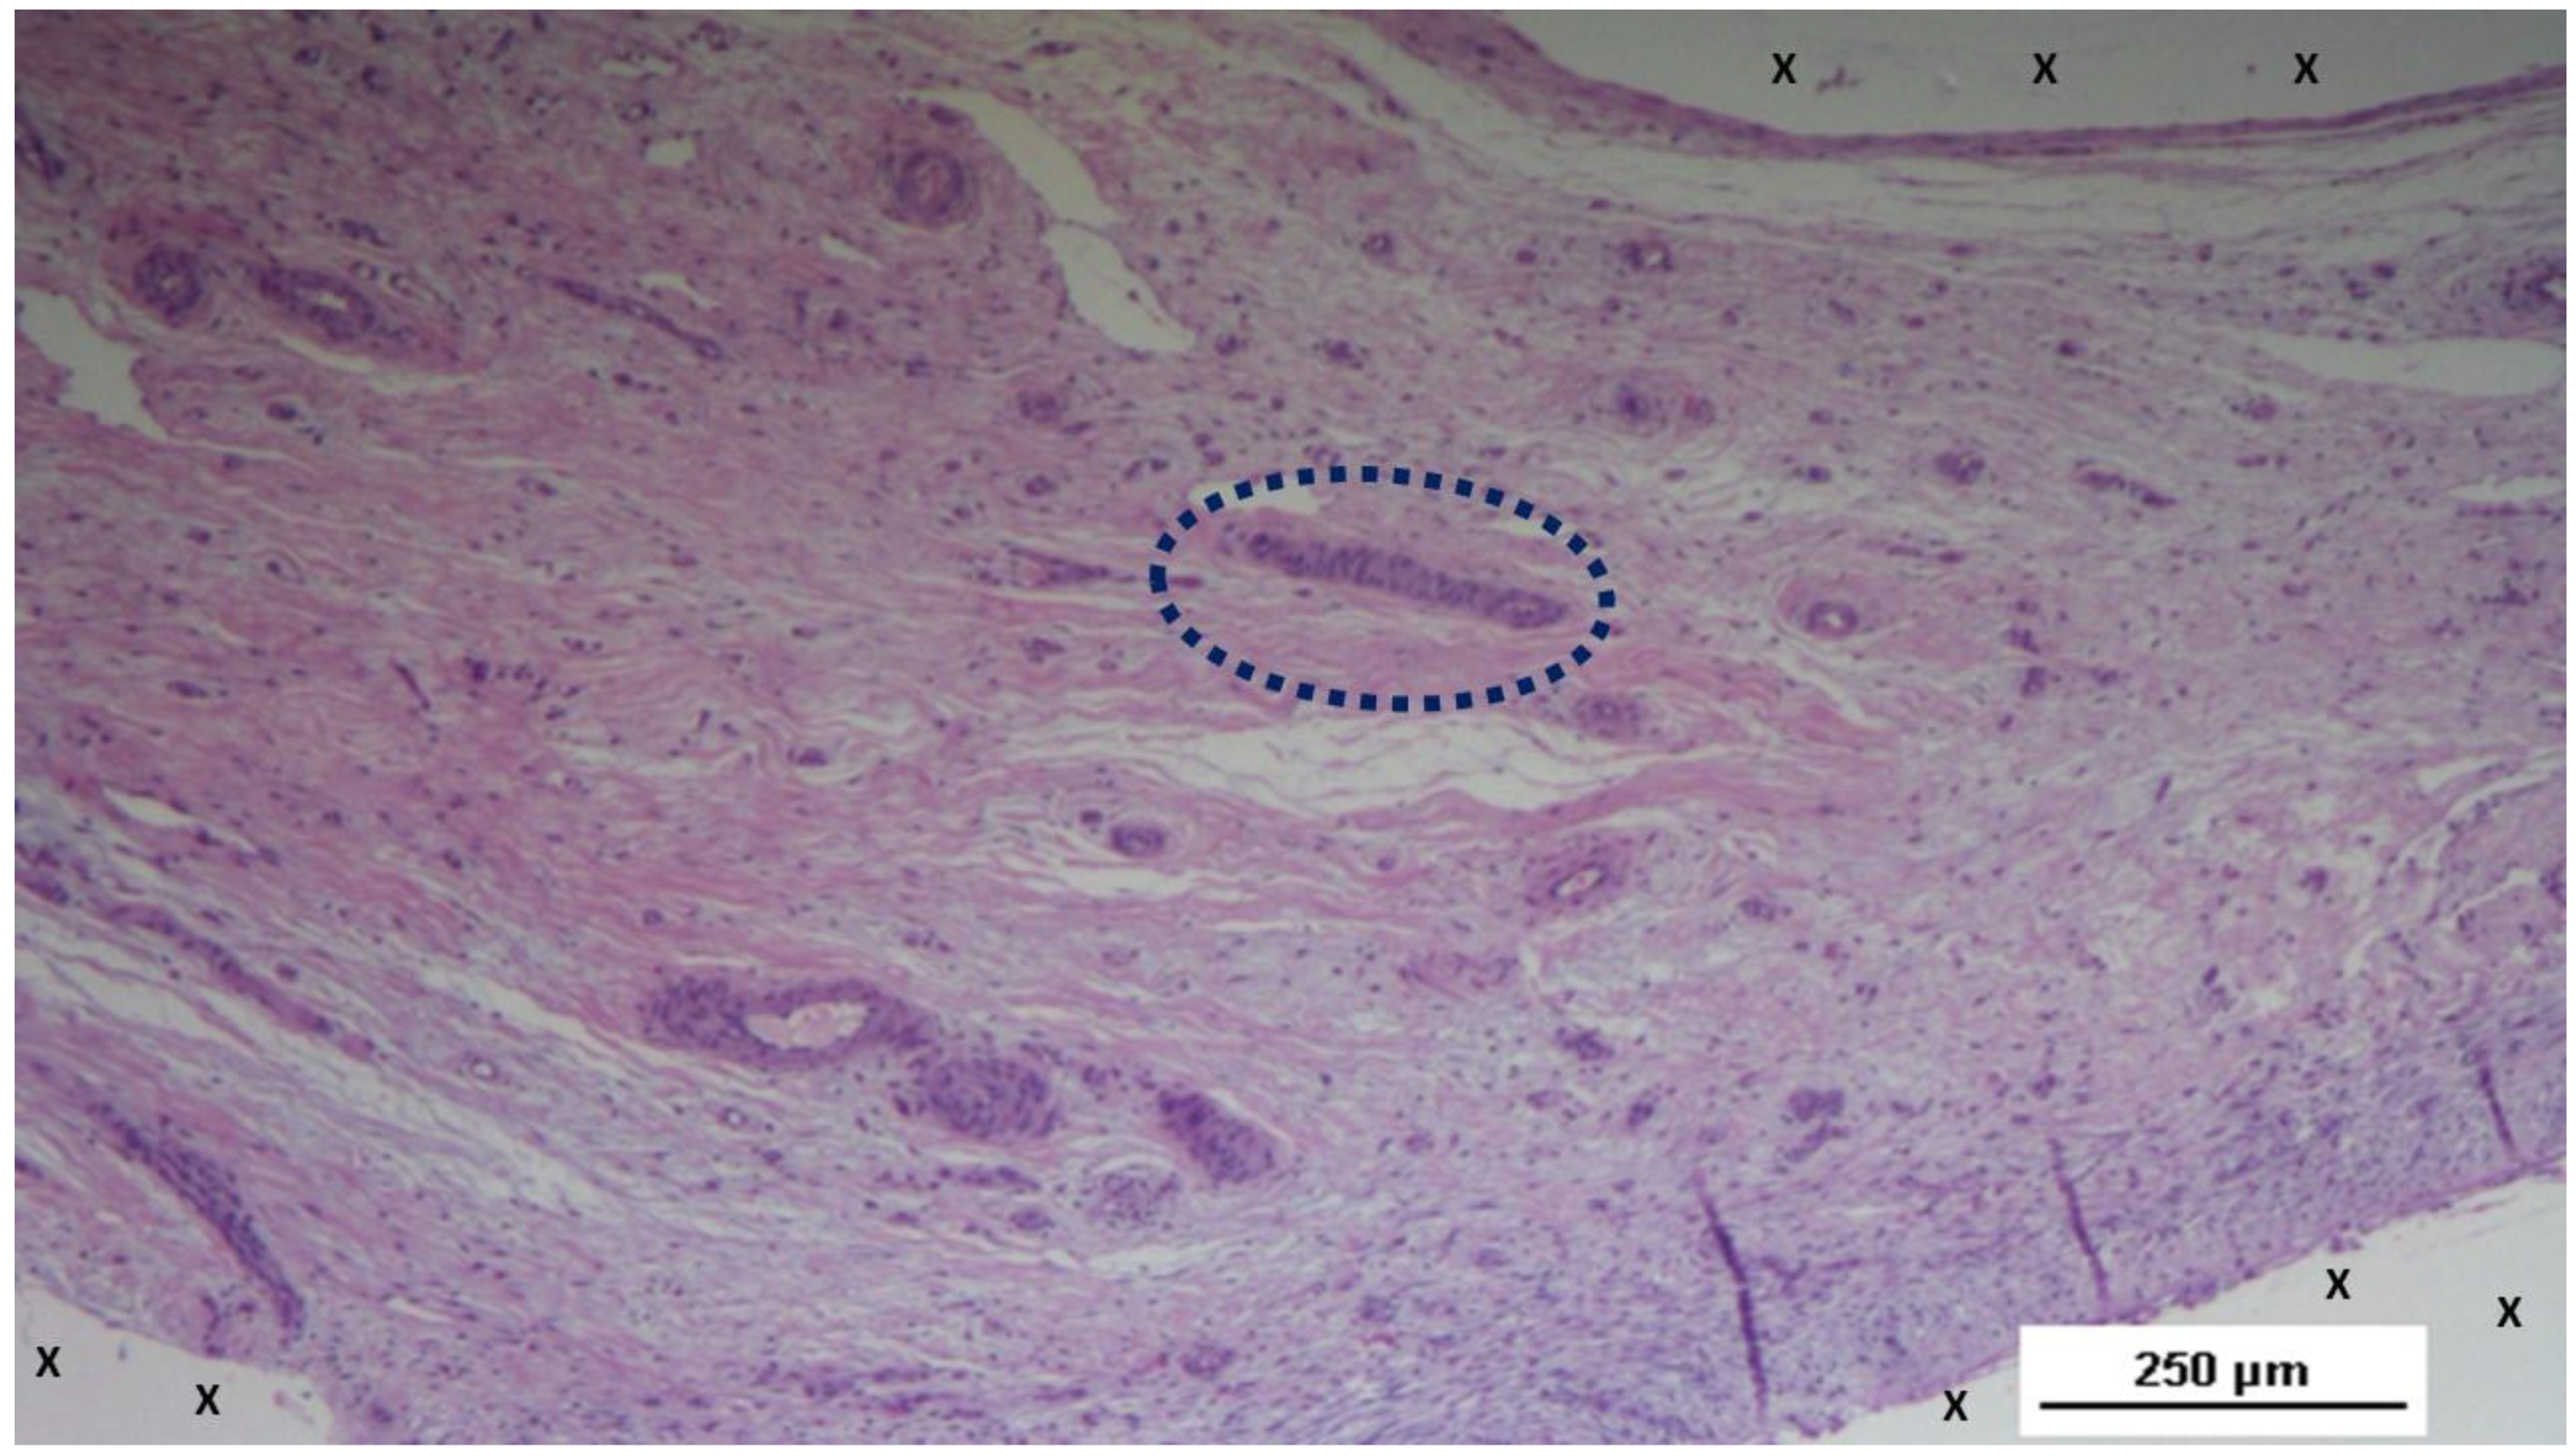

Figure 7. - Biopsy sample excised 3 months post-op: Within the fabric of the 3D scaffold of the S&S Hernia System (X), amidst loose, well-hydrated connective tissue and numerous vascular elements, a large elongated nerve structure (blue circle) in an advanced stage of development is evident. The nerve axons are enveloped by a thick myelin sheath. The 3D scaffold exhibits no inflammatory reaction. HE 100X.